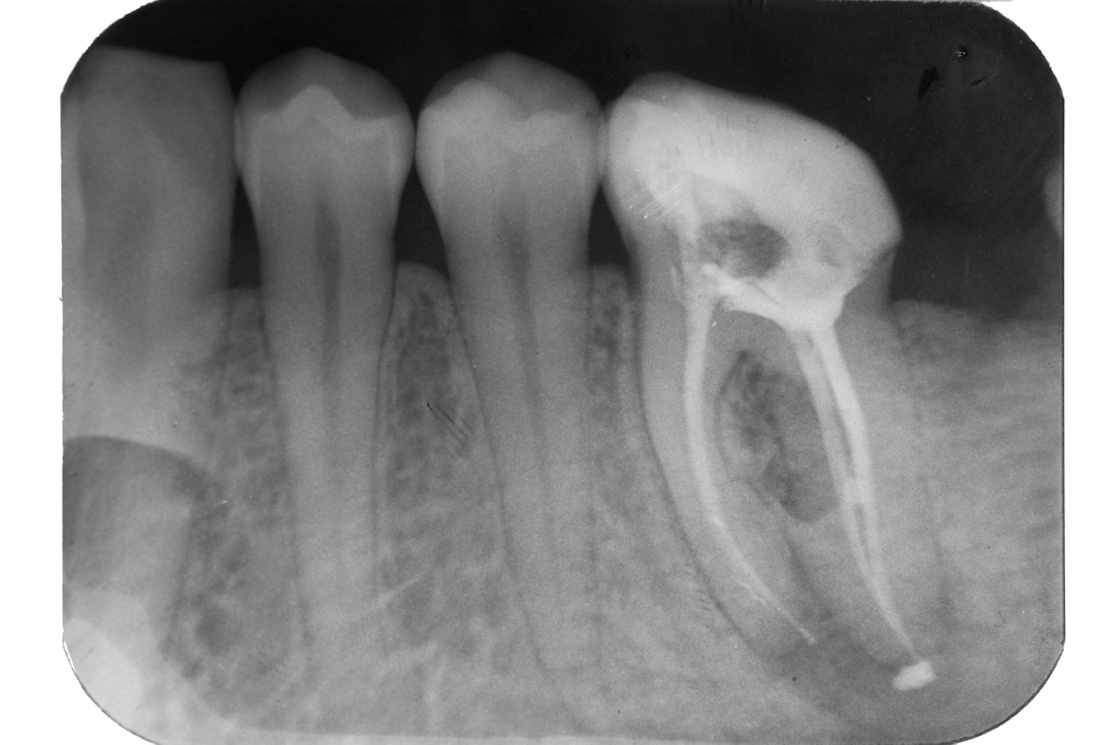

Пациентка 40 лет обратилась в клинику с целью осмотра перед протезированием. На прицельной рентгенограмме (рис 2а) нижнего первого моляра отмечается неполная обтурация корневых каналов. Во втором моляре, вероятно, ранее также было проведено эндодонтическое лечение, о чем свидетельствует наличие пломбировочного материала в полости зуба, но каналы не обурированы. Лечение: удаление старых пломб, создание доступа к устьям корневых каналов, в первом моляре проведено распломбирование корневых каналов, во втором моляре проведена ревизия корневых каналов. После тщательной инструментальной и медикаментозной обработки корневых каналов запломбировали корневые каналы.

Рис. 2 а Рентгенологический снимок до лечения

Рис. 2 б Рентгенологический снимок после пломбирований корневых каналов

На контрольной рентгенограмме (рис. 2б) корневые каналы моляров герметично обтурированы на всем протяжении до верхушек.